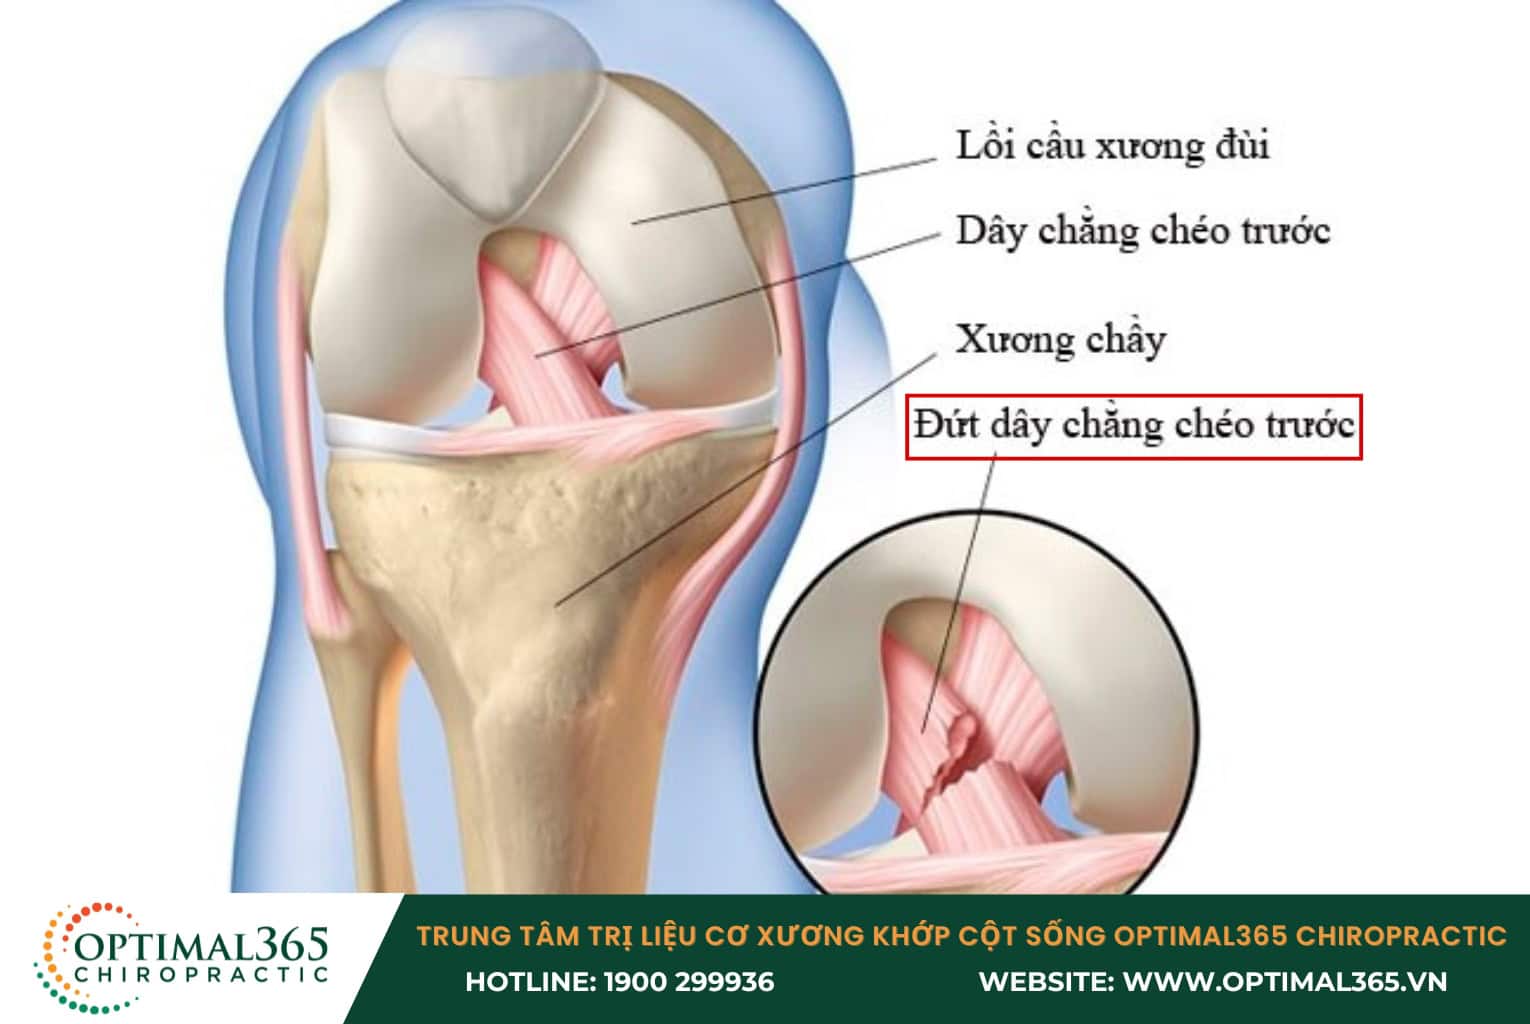

Chấn thương dây chằng đầu gối chéo trước (ACL)

Chấn thương dây chằng chéo trước thường xảy ra khi khớp gối bị trẹo do thay đổi hướng đột ngột, dừng lại một cách bất ngờ, tiếp đất không đúng cách sau khi nhảy hoặc khi có va chạm mạnh như trong tai nạn xe cộ hoặc các sự cố sinh hoạt hàng ngày. Chấn thương này thường gặp trong các môn thể thao cường độ cao như bóng đá, bóng rổ và bóng chuyền.

Khi dây chằng chéo trước bị tổn thương, người bệnh có thể nghe thấy tiếng “rắc” từ khu vực đầu gối và cảm nhận được sự lỏng lẻo ở vùng này. Các triệu chứng điển hình của chấn thương dây chằng chéo trước bao gồm:

- Sưng tại khu vực gối trong vòng 24 giờ, cần chườm đá lạnh và giữ gối ổn định để giảm sưng.

- Đau dữ dội ở phía trước gối, đặc biệt khi di chuyển.

- Hạn chế khả năng vận động của khớp gối.

- Teo cơ xung quanh gối, dẫn đến sự yếu dần của khớp.